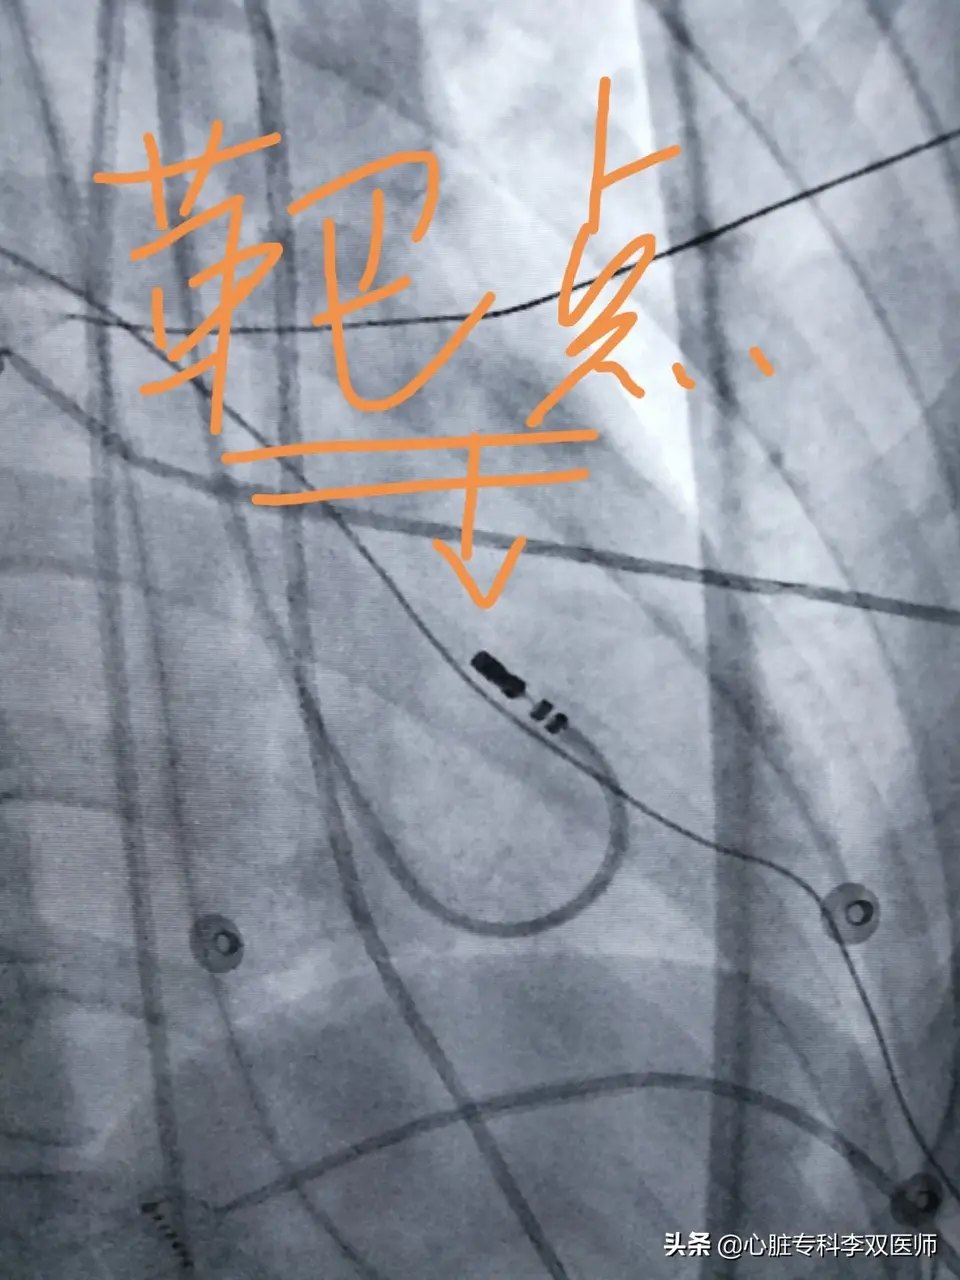

前天给一个外地来就诊的病人做了难度很高的“心外膜室早”消融的病例,病人一年前在杭州某三甲医院曾行消融失败,这一年来因为笼罩在“频发室早”的阴影下,患者有了明显的心理问题。这次我们标测的情况和上次外院消融情况完全一致,只是坚持又带有一点运气的在非传统的消融位置(解剖位置,而不是最早激动位置)尝试了消融,结果异常的顺利,术中忐忐忑忑观察了一小时无复发。今天患者顺利出院,术后24小时心电图提示的室早仅2次(一天的心跳是约10万次,1000次以内的早博没有意义),比机器的误差都小,而术前是1.4—2.8万次,是万!万!万!。坚持就是胜利,坚持带来好运!